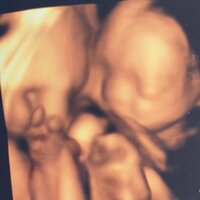

続けて「期待を胸に、じろの3D4Dエコーを見てみましょう!」と第2子のエコー写真を公開し「ん~~~わかりにく~」とコメント。「どうやら桃の話では、今日は良い感じのエコーが撮れなかったそうです」と説明し「先生も結構粘ってくれたらしいのだが」と補足した。

また「辛うじて顔面が分かるのもあったり無かったり」と別のエコー写真も公開。最後に、息子について「今や爆発寸前ムチムチボディになってるんだから、生命って、赤ちゃんって、不思議なものですね」とつづり、ブログを締めくくった。